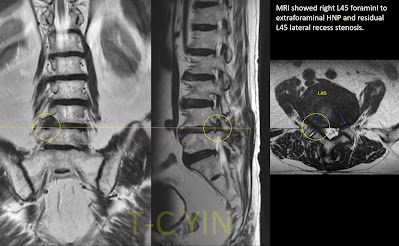

核磁共振檢查後,確實有明顯的腰椎第2-3,3-4以及第4-5節的椎管狹窄神經壓迫 (spinal stenosis)